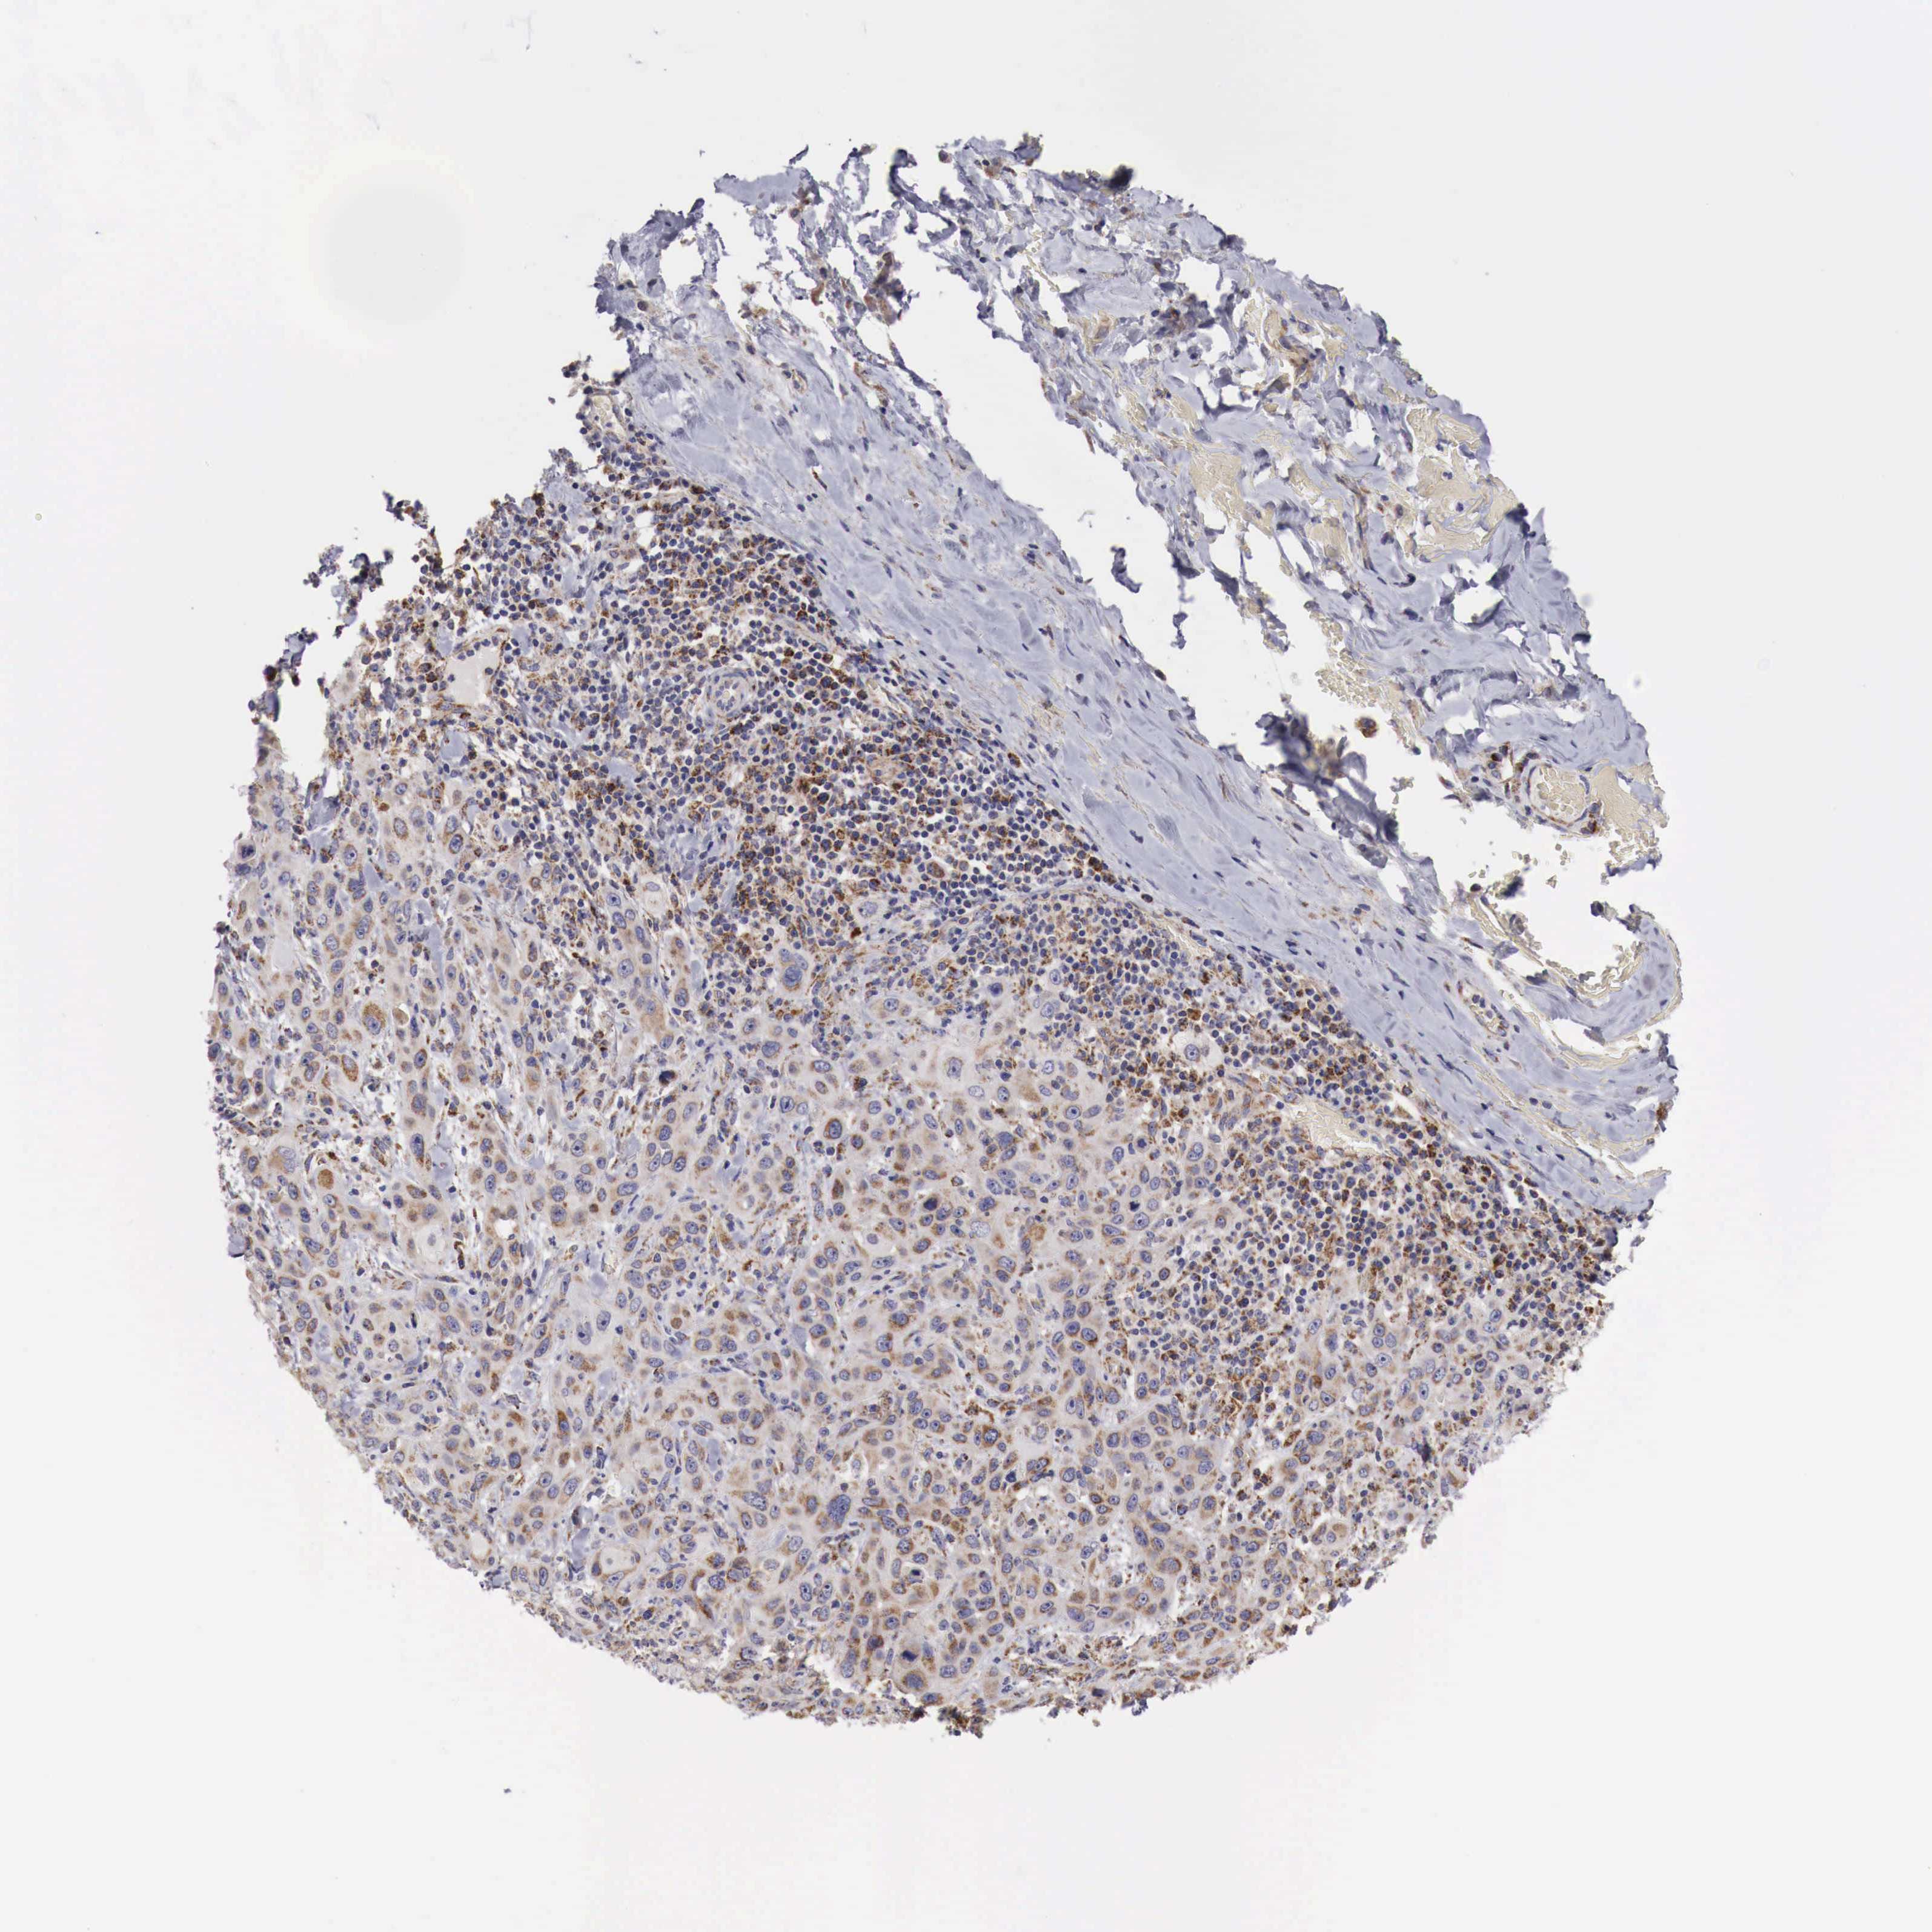

SKIN CANCER - Protein expressioni

A mouse-over function shows sample information and annotation data. Click on an image to view it in a full screen mode. Samples can be filtered based on level of antibody staining by selecting one or several of the following categories: high, medium, low and not detected. The assay and annotation is described here.

Each image is clickable and will lead to virtual microscopy that enables deeper exploration of all samples and also displays staining intensity scores, fraction scores and subcellular localization as well as patient and tissue information for each sample.

Antibody HPA000527

Staining

High

Medium

Low

Not detected

Intensity

Strong

Moderate

Weak

Negative

Quantity

>75%

75%-25%

<25%

None

Location

Nuclear

Cytoplasmic/membranous

Cytoplasmic/membranous,nuclear

Squamous cell carcinoma, NOS

Basal cell carcinoma